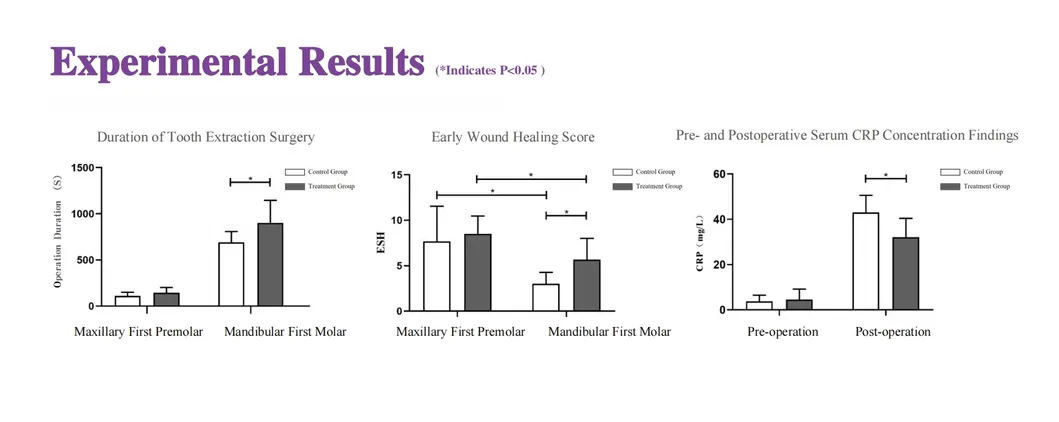

In this groundbreaking study, dogs were selected to assess the effectiveness of the Golden Cudgel-Pneumatic Dental Elevator Kit. Researchers meticulously documented physiological parameters, extraction duration, and socket damage compared to traditional manual devices. The data provides profound insights into the superior performance and efficiency of these advanced dental tools.